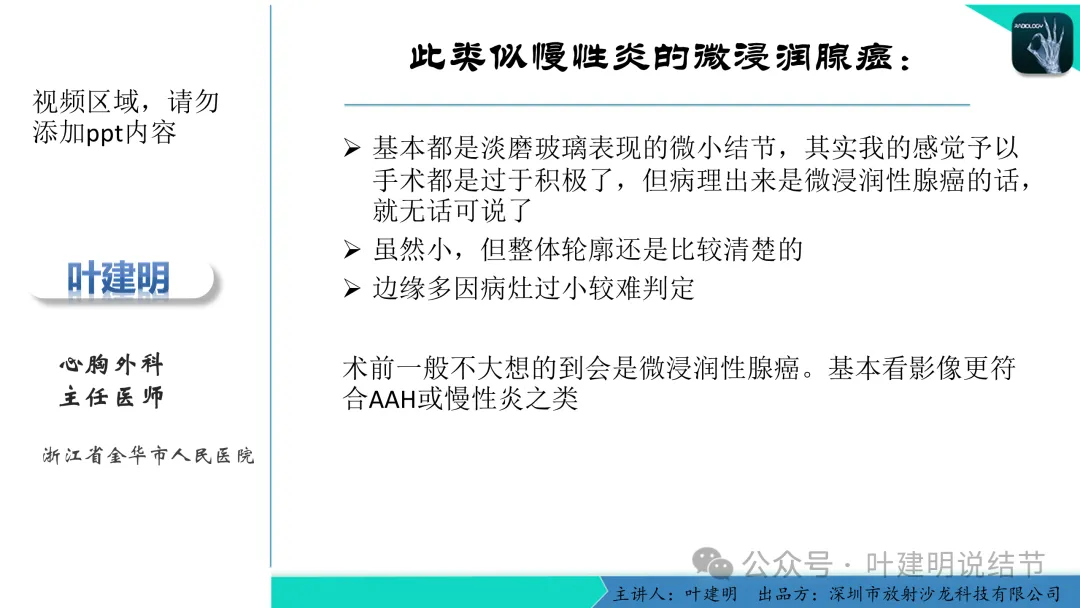

早在2020年时,我受邀在《放射沙龙》做过一个系列的精品课,当时专门总结分析过各类良恶性肺结节与肿块的影像特征,这是当时关于微浸润性腺癌影像特征的分析,今天看来仍基本不太需要改变,大家有兴趣的可以参考: